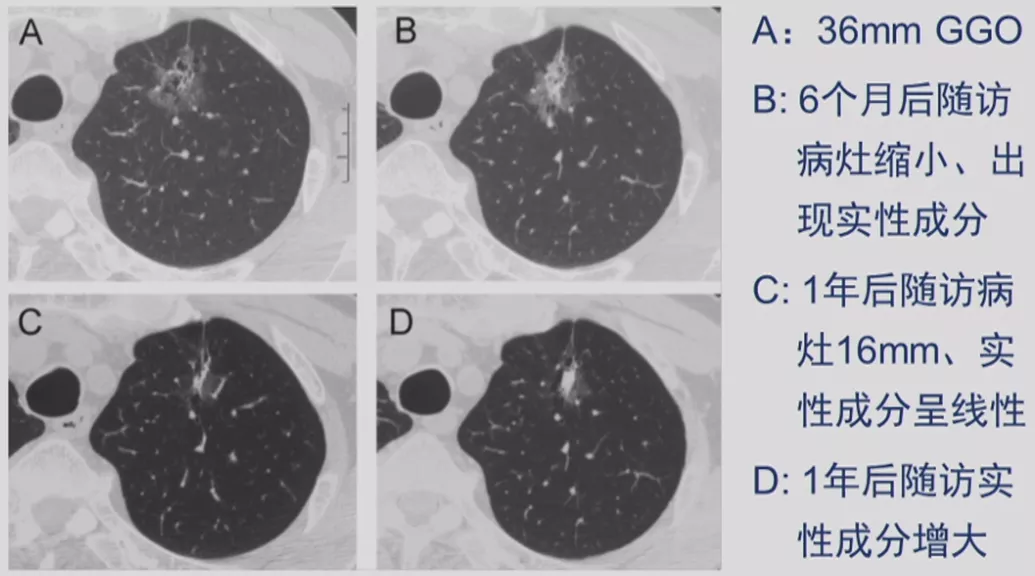

GGO

我们再谈一下GGO的问题。刚才谈到了GGO是一个动态的变化,可以先是磨玻璃样的结节,逐渐有实性成分,最后实变。GGO如果出现实性成分的话,一定要提高警惕。

GGO自然变化与随访结果

基本上是这几种随访结果:第一种,结节没有变化;第二种,实性成分增多;第三种,结节消失。后两种都好处理,关键是没有变化的GGO,下一步该怎么办呢?国际上建议,GGO观察三个月,如果持续存在,结节实性成分>5mm可以手术;大小长到了1.5cm,要密切观察或者直接手术;如果稳定至少要观察三年。如果是混合性实性结节,实性成分>5mm可以手术;如果大小>15mm可以手术,针对不同的情况,都有不同的规定。

CT随访

1)病灶大小无变化、实性成分增多

这个结节大小没有太大变化,实性成分增多,这不是一个好征象,可以考虑手术。

2)病灶缩小、出现实性成分

容易被大家忽略的是结节的大小变小,但实性成分增多,值得大家重视。不要认为结节变小了就一定是良性。